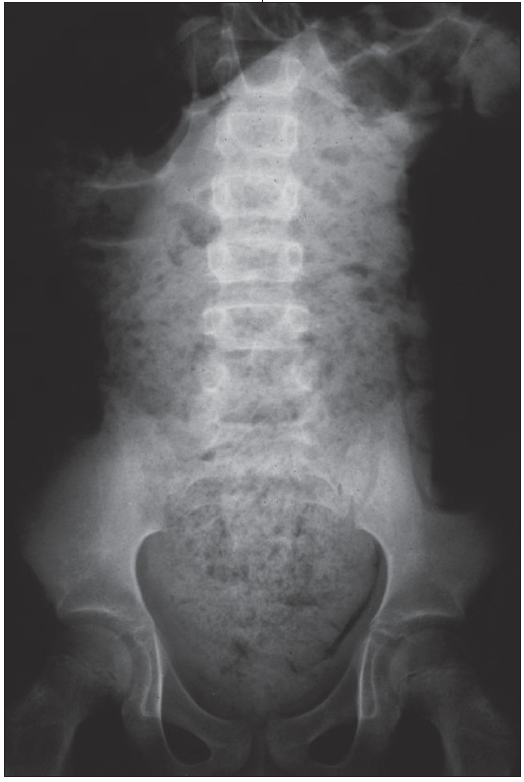

Evaluation of encopresis is similar to that of constipation and includes a thorough history and physical examination with assessment for potential organic causes. In most cases, laboratory evaluations are unnecessary. Although a radiograph may not be needed to make the diagnosis, it can be a helpful adjunctive tool during the educational process (Figure). A radiograph can be used to demonstrate the large amount of retained stool, which can help parents understand the pathology. If an organic cause is suspected, referral to a gastroenterologist or other appropriate specialist is recommended.